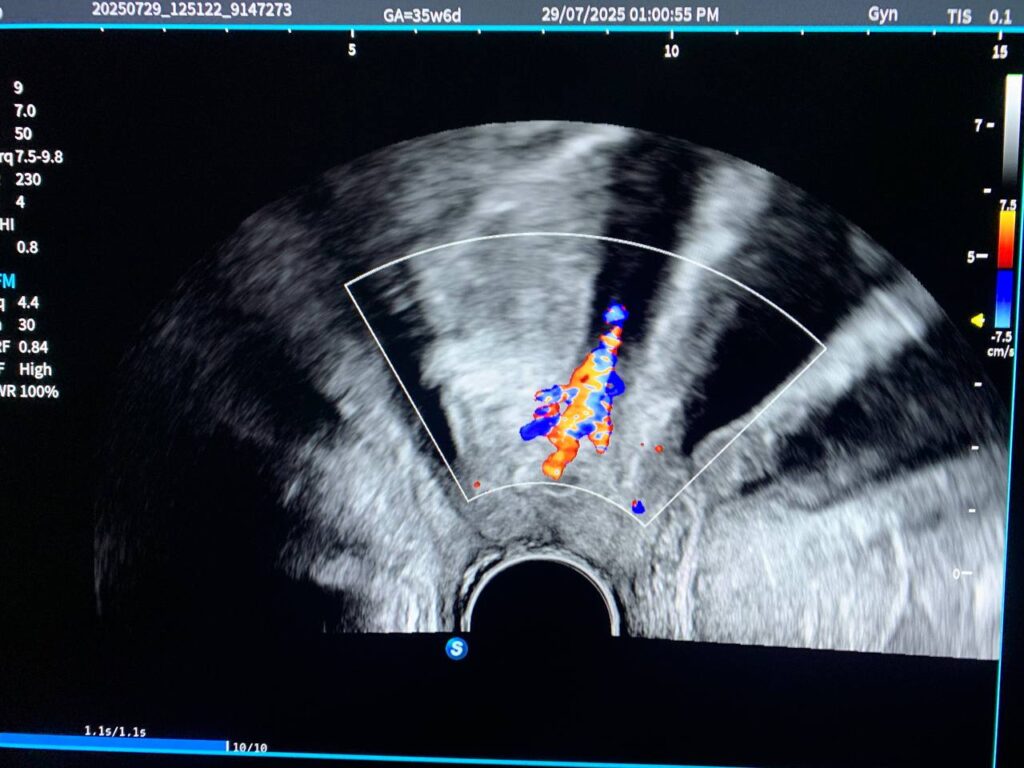

· Bulky uterus, endometrial lining thickness 6.2mm, with presence of isoechoic vascular solid mass within the cervical canal, its size >43x30mm, mostly pedunculated submucosal fibroid arise from posterior junctional zone , nearly at level of lower body